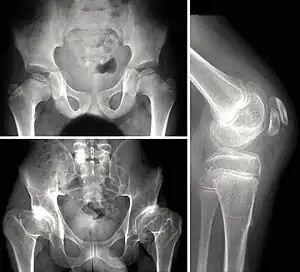

Children with autosomal dominant MED experience joint pain and fatigue after exercising. Their x-rays show small and irregular ossifications centers, most apparent in the hips and knees. There are very small capital femoral epiphyses and hypoplastic, poorly formed acetabular roofs.[1] A waddling gait may develop. Knees have metaphyseal widening and irregularity while hands have brachydactyly (short fingers) and proximal metacarpal rounding. Flat feet are very common.[2] The spine is normal but may have a few irregularities, such as scoliosis.